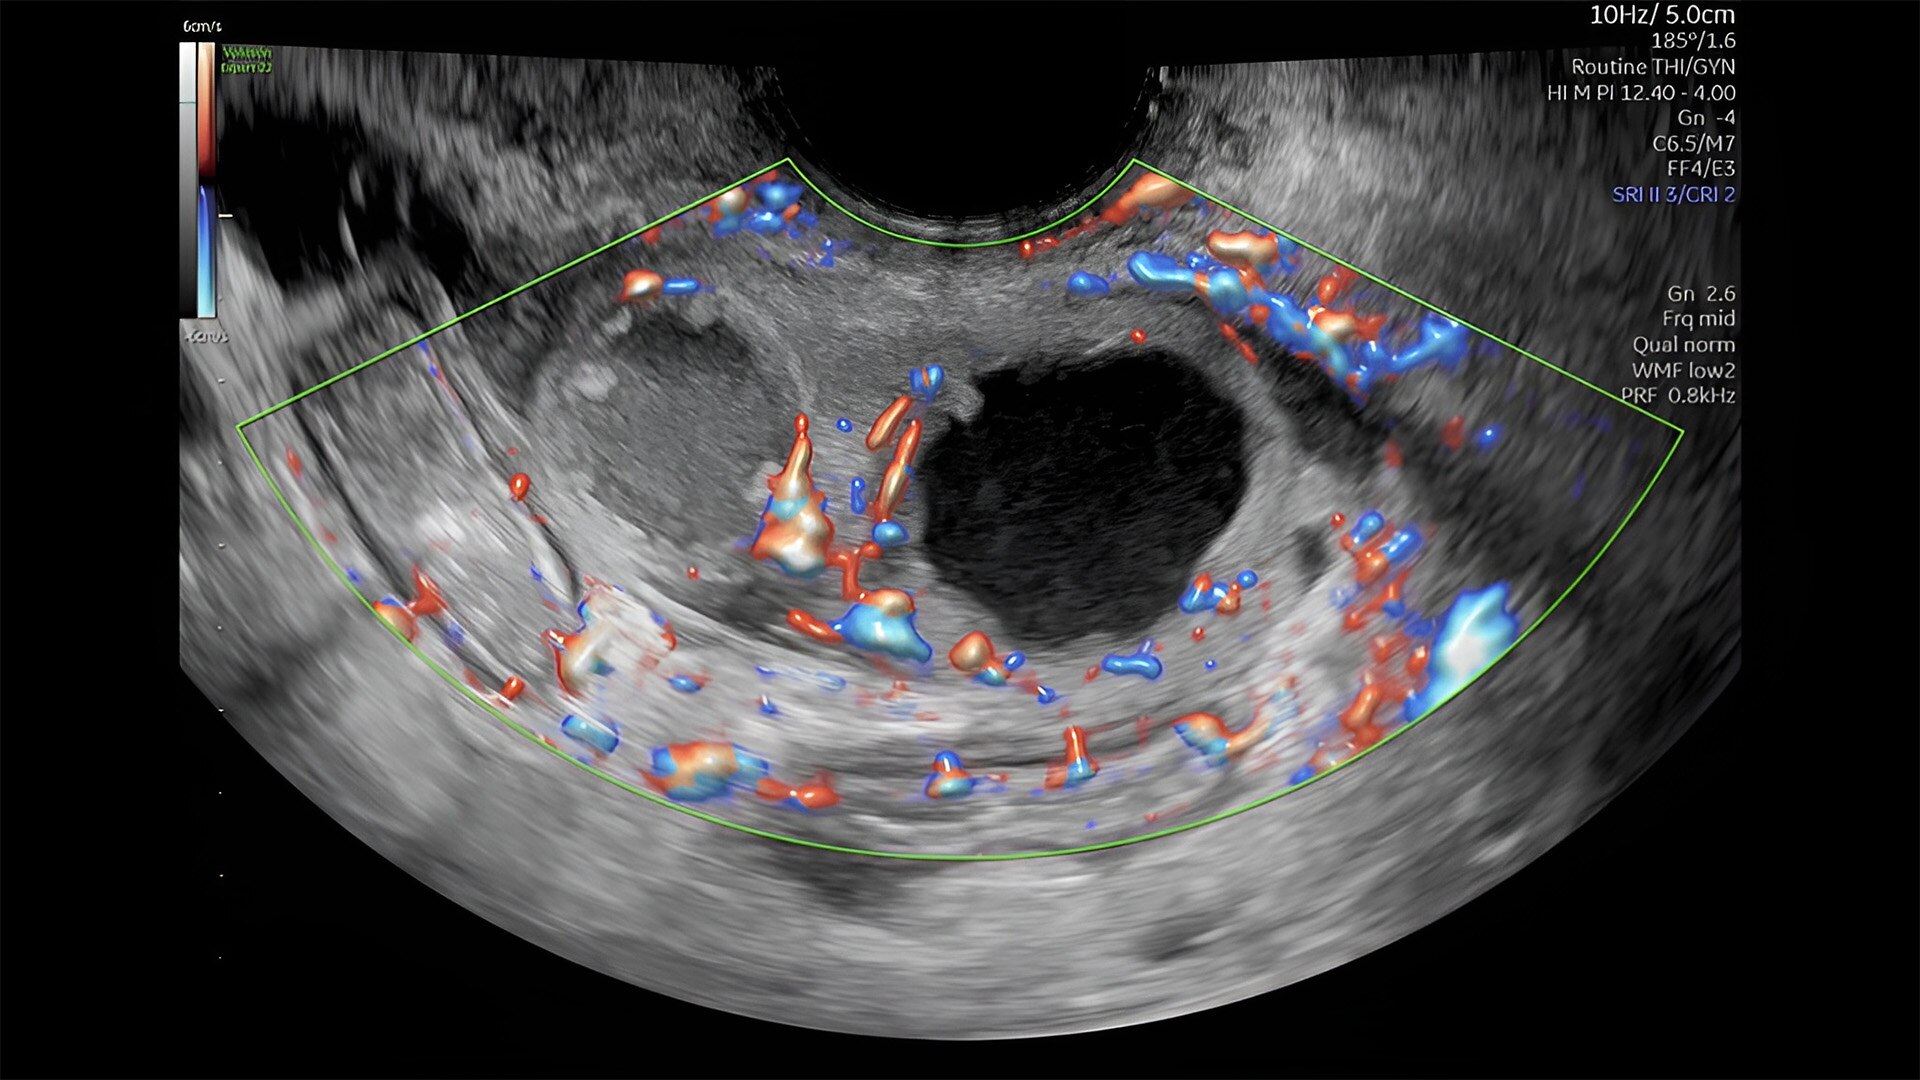

Pelvic health

Offer patient answers faster with Ai-based automation tools